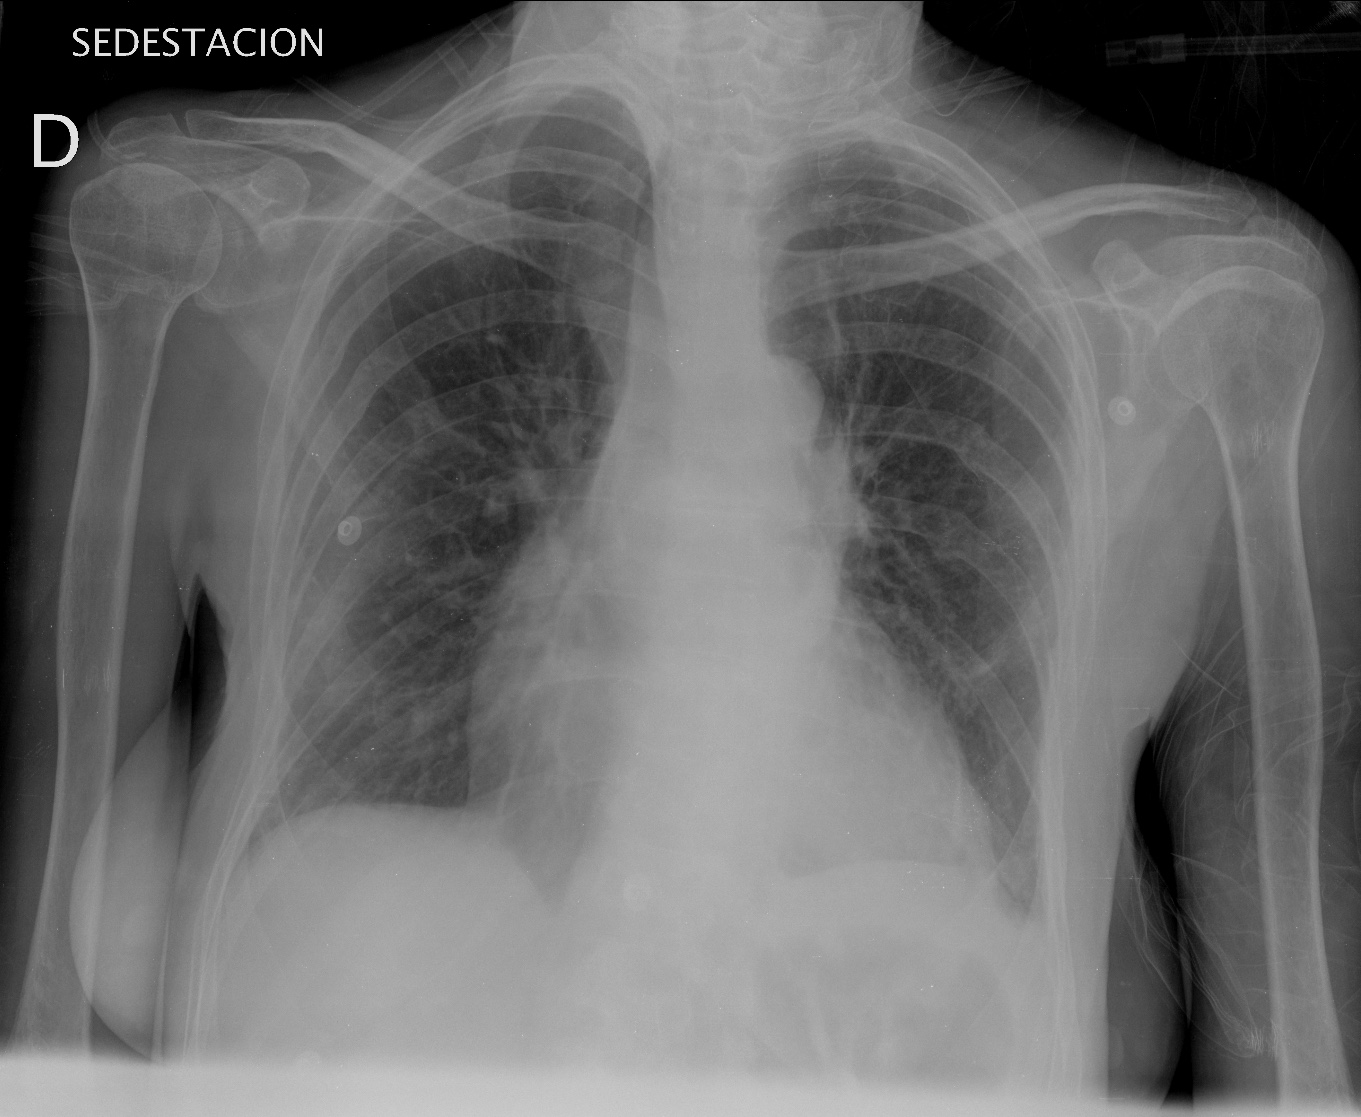

Mismo paciente, al cual esta vez se le ha tomado una radiografía en PA y en sedestación. Observar como las clavículas están equidistantes a las apófisis espinosas y como ha desaparecido el velamiento del pulmón izquierdo.

Por otra parte, paciente presenta una cardiomegalia y un discreto ensanchamiento del mediastino es probable relación con cambios postquirúrgicos.